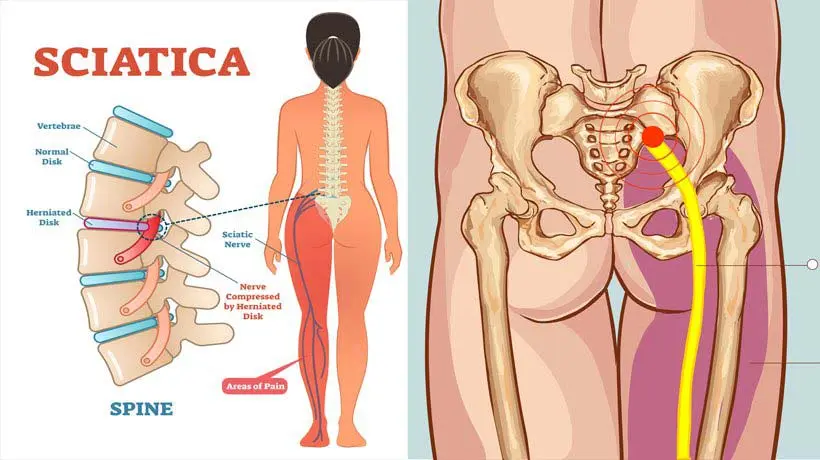

سیاتیک و درد کمر

سیاتیک یکی از شایعترین دلایل انواع کمردرد است که به علت فشار بر عصب سیاتیک ایجاد میشود. این درد معمولاً از کمر شروع شده و به باسن و پاها انتشار مییابد. بیماران اغلب از بیحسی، سوزنسوزن شدن یا ضعف پاها شکایت دارند.

فیزیوتراپیستها با تمرینات اصلاحی، کشش عضلات و استفاده از دستگاههای تخصصی، به کاهش فشار روی عصب سیاتیک کمک میکنند. درمان سریع این مشکل از بروز عوارض جدیتر جلوگیری خواهد کرد. در موارد شدید، ممکن است جراحی لازم باشد.